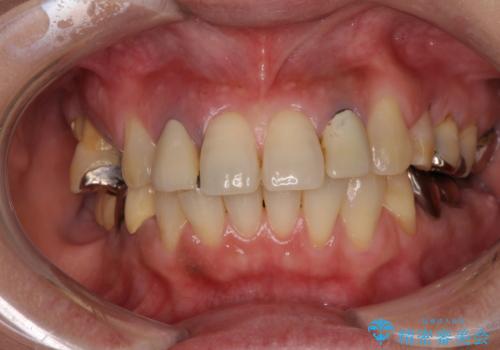

- 歯が破折しているため、抜歯が必要であると近医で診断されてからも放置を続けてしまったとのことで来院された患者様です。

臼歯はもはや咬み合わせに寄与していない状態であり、3歯を抜去してインプラント2本埋入によるブリッジ補綴を計画しました。

セオリーとしては、インプラント補綴治療により奥歯の咬み合わせを確立してから、前歯部の処置を行うことになりますが、初めてのインプラント治療であることや、前歯部の見た目が気になっていることから、前歯の抜歯即時埋入インプラントによる補綴治療を先行して行い、並行して奥歯のインプラント治療を進めて行くこととしました。